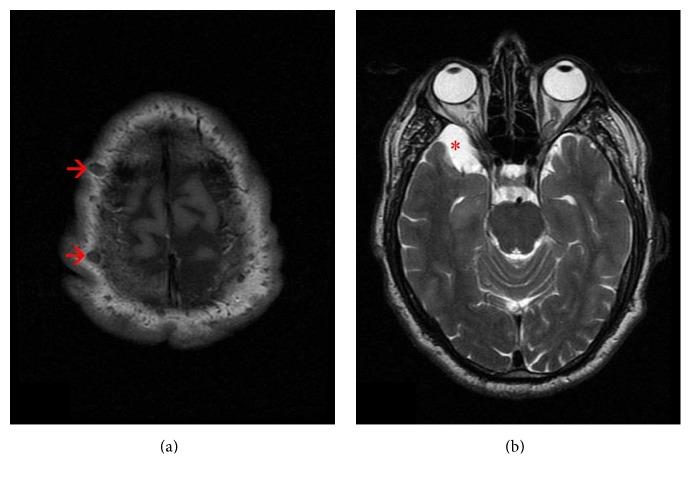

Ankylosing spondylitis (AS) is a systemic disease primarily characterized by the inflammation of sacroiliac joints and axial skeleton. Neurofibromatosis type 1 (NF1) is a multisystem genetic disease which is characterized by cutaneous findings, most importantly café-au-lait spots and axillary freckling, by skeletal dysplasia, and by the growth of both benign and malignant nervous system neoplasms, most notably benign neurofibromas. In this case report, we present a 43-year-old male with AS and NF1.

强直性脊柱炎(AS)是一种全身性疾病,主要特征为骶髂关节和中轴骨骼的炎症。1型神经纤维瘤病(NF1)是一种多系统遗传病,其特征包括皮肤表现,最重要的是牛奶咖啡斑和腋窝雀斑,骨骼发育异常,以及良性和恶性神经系统肿瘤的生长,最显著的是良性神经纤维瘤。在本病例报告中,我们介绍了一名患有AS和NF1的43岁男性。